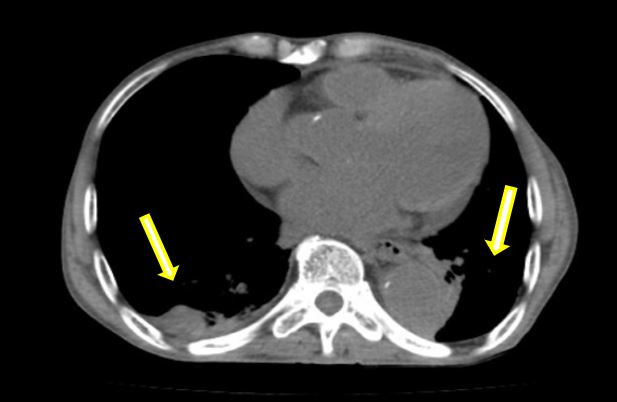

巨大假性动脉瘤压迫左肺(箭头示)

在患者转运过程中,血管外科急诊团队、影像科、麻醉科、胸心外科、导管室、输血科等相关科室已着手做好了急诊相关预案。从患者的急诊CTA上可以看到原有的胸主动脉支架因血流动力学影响,出现了近端Ⅰ型内漏,大量血液经由支架与主动脉间的缝隙进入假性动脉瘤腔内,左侧胸腔出现大量血肿,甚至出现了少量的心包积液。急诊血常规显示患者血红蛋白才66g/L,颜老爷子已出现烦躁不安等谵妄表现,为保障手术安全,团队立即联系输血科郑春盛主任,有力地保障了患者术中用血。